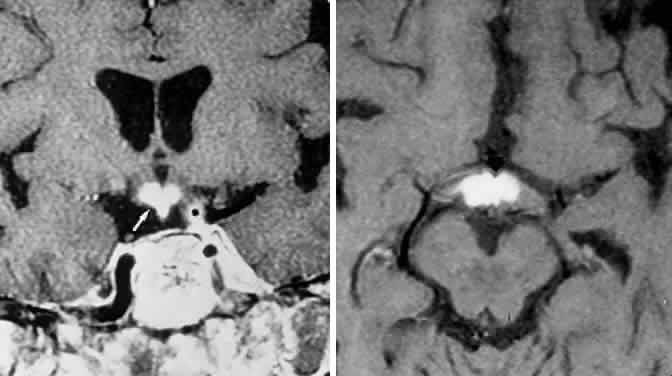

Clinical signs and symptoms include the following: acute onset of severe headache, often sickening frontal or retro-bulbar cephalgia, or other less disabling change in headache pattern; acute or rapidly progressing unilateral or bilateral (usually asymmetric) ophthalmoplegia due to rapid expansion into cavernous sinuses (see also Volume 2, Chapter 12); epistaxis or CSF rhinorrhea when the mass ruptures or erodes into the sphenoid sinus; complications of blood or necrosis debris in the CSF, with “pseudomeningitis”; rapid neurologic deterioration and obtundation, although patients need not be stuporous; and, greater or lesser degrees of hypopituitarism.62,63 Selective expansion laterally into the cavernous sinus may produce ophthalmoplegia without visual loss; selective expansion superiorly may produce visual loss without ophthalmoplegia. Almost without exception, enlargement of the sella is found even on plain skull film views; both CT and MRI detect fresh hemorrhage (Fig. 3), but MRI may fail to demonstrate acute hemorrhage unless specific sequences are employed (hemorrhage may be isointense on T1-weighted images and hypointense on T2-weighted images; in the subacute phase, extracellular methemoglobin should appear bright on both T1 and T2 sequences). Corticosteroid replacement and other supportive measures may be critical, and, in most instances, decompression through the sphenoid sinus is advisable, sooner rather than later. Bromocriptine has been suggested as a temporizing measure when signs and symptoms are modest and not progressing,64 and there are advocates65 for conservative management consisting of intravenous dexamethasone, so long as visual deficits are minimal or rapidly improve; otherwise decompressive surgery is required. Given the regularity with which pituitary apoplexy is often a delayed diagnosis, being confused with ruptured aneurysm or meningitis, for example, and that transsphenoidal surgery is a relatively simple undertaking, further procrastination in decompression of the compromised visual pathways is to be avoided.

Fig. 3. Neuroimaging of pituitary adenomas. A. Axial computed tomography (CT) section shows a round tumor mass filling the suprasellar cistern; ring enhancement (arrows) indicates subcapsular hemorrhage. B. Contrast-enhanced coronal CT section through a large invasive adenoma. Note encasement of the carotid artery (arrows) and the position of the middle cerebral artery above (arrowheads). C. Axial CT section shows lateral expansion into the cavernous sinuses (white arrows) and a necrotic cyst (black arrow). D. Subfrontal superior extent of the mass. Note the middle cerebral arteries. E. Magnetic resonance imaging of a large lobulated prolactinoma, with suprasellar extension. Note the distortion of the third ventricle (open arrows) and extension toward the temporal lobe (long arrow); the tumor has not involved the sphenoidal sinus (s). F. Chiasm (arrowheads) is draped on the superior surface of the tumor (TR, 550 milliseconds; TE, 26 milliseconds). G. Sagittal section shows suprasellar growth with the chiasm above (arrowheads); the sella (arrows) and sphenoidal sinus (s) are normal (TR, 850 milliseconds; TE, 26 milliseconds). H. Hyperintense signal (TR, 2000 milliseconds; TE, 60 milliseconds) indicates the partial cystic character. Sagittal (I) and axial (J) sections with head tilt to the right, in case of a large cystic adenoma with an interface level between newer blood (white arrow) and older blood (black arrow) (TR, 800 milliseconds; TE, 30 milliseconds). K. Signal difference is intensified (TR, 2100 milliseconds; TE, 80 milliseconds). L. Hemorrhage (bright signal, arrow) in a pituitary adenoma with headache and bitemporal field depressions. M. Without interventions, 2-month follow-up showed spontaneous involution, with normal pituitary gland (arrow), stalk, and chiasm.